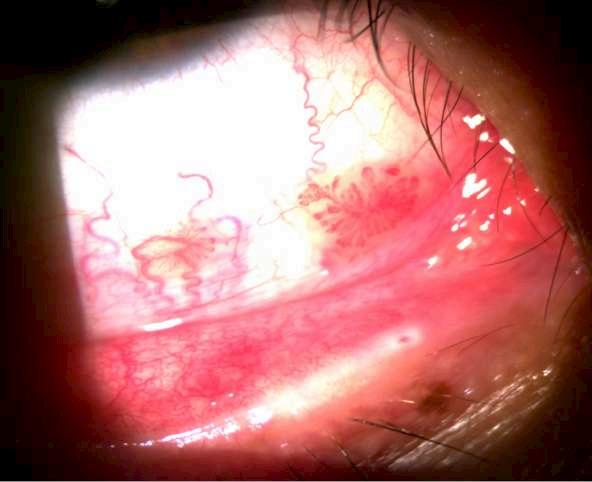

1.A. GRANULOMA PIÓGENO

Imagen aportada por Dr. Álvaro Rodriguez

Bü Lesión pedunculada y aspecto papilomatoso de color sonrosado que se desarrolla después de un trauma quirúrgico, accidental o un proceso inflamatorio local (chalazión o reacción a cuerpo extraño)

ü EL diagnóstico diferencial debe realizarse principalmente con un papiloma pediculado, con el que generalmente le diferencia la velocidad de progresión y el antecedente de traumatismo o chalazión.

Imagen A y B muestran un granuloma a nivel del canto medio del ojo derecho.